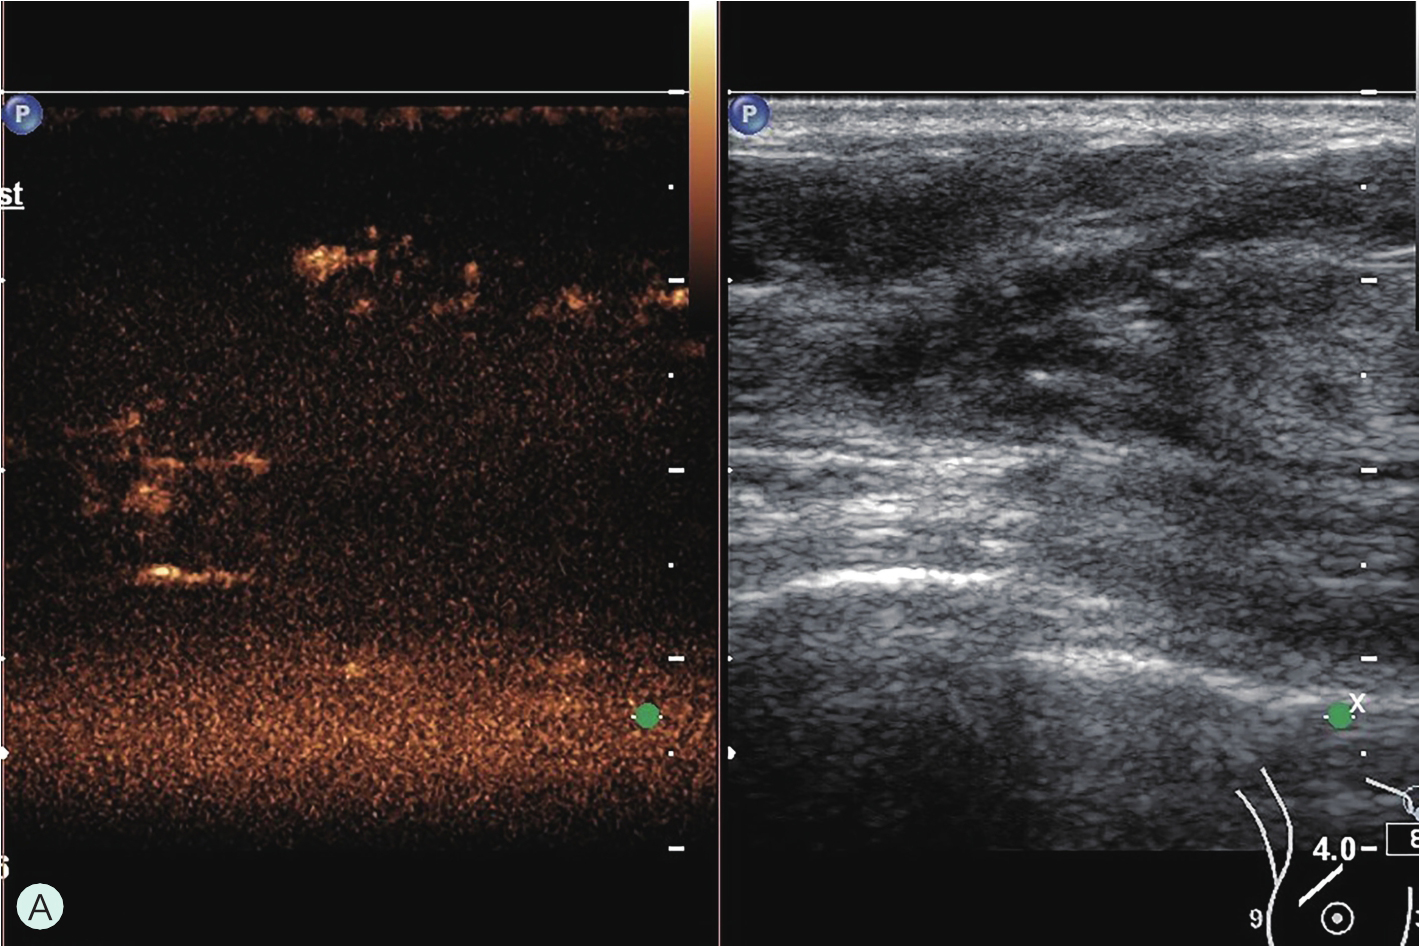

所有具有超声造影功能并支持浅表线阵探头造影的超声诊断仪器均可用于乳腺超声造影检查。由于乳腺超声造影对设备的造影效果、探头选择及参数调节要求很高,故在开展乳腺超声造影前,必须充分论证其造影效果,与设备应用专员共同调节造影参数至乳腺超声造影最佳模式。常规高频线阵探头不能用于乳腺超声造影,而必须选用低频线阵探头。下面将根据笔者所在单位临床工作实际,列举几种超声仪器的乳腺超声造影参数及所用探头供读者参考(图2-1-3~图2-1-7)。

图2-1-4 PHILIPS IU ELITE乳腺超声造影参数及所用探头

A.PHILIPS IU ELITE乳腺超声造影参数;B.PHILIPS IU ELITE乳腺超声造影探头L9-3